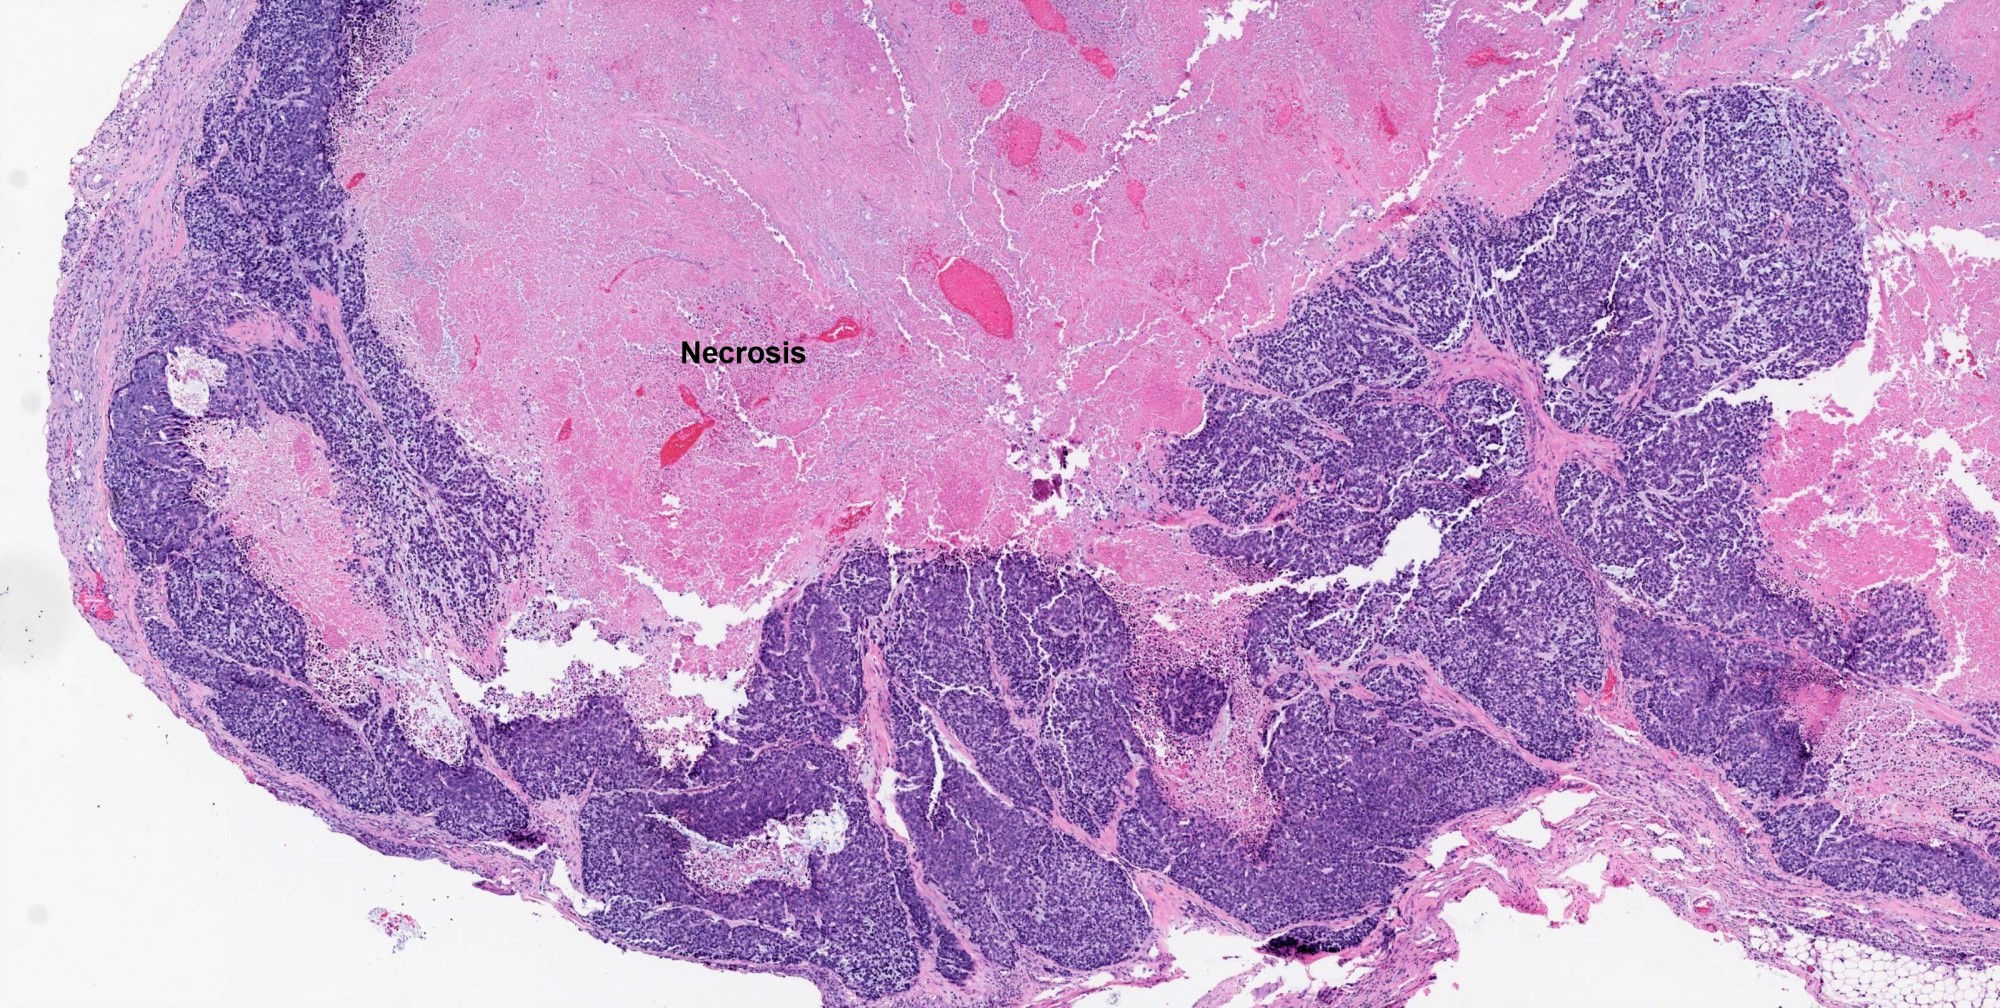

- Invasiveness is typically demonstrated as expansile invasive multinodular growth: myoepithelial carcinoma rarely shows infiltration of single cells / small clusters or desmoplastic reaction

- Nodules often have a hypocellular center with hyalinized stroma or bland necrosis surrounded by a hypercellular peripheral zone

- Tumor necrosis can be seen within the hypercellular central zone of a tumor nodule

- Currently, there is no well defined, widely accepted grading system: presence of tumor necrosis is considered by some as a feature of high grade myoepithelial carcinoma (Am J Surg Pathol 2015;39:931)

Contributed by Abeer Salama, M.D. and Bin Xu, M.D., Ph.D.